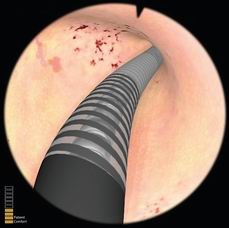

宫腔镜手术模拟器用来模拟临床宫腔镜手术,培训医师宫腔镜手术标准操作。系统可模拟宫腔镜在子宫内的进出、液体流量的控制、镜头的调节、镜头的旋转、器械的旋转、环形电极的使用等等。系统可模拟正常组织、病理组织、软组织损伤等。操作不当可引起出血、液体压力过高等并发症。操作时有力反馈手术手感,可对操作过程评估、打分。

宫腔镜检查模块

可进行正常、异常子宫的各项检查,让学员在安全的环境中学习、掌握冲水、控制内镜检查整个宫腔等基本操作